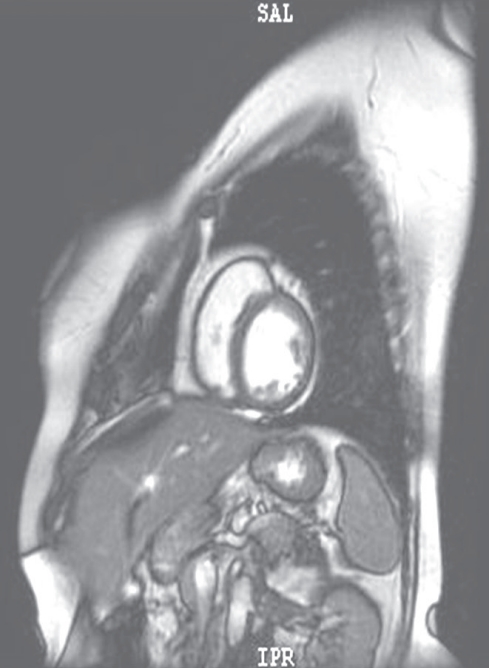

摘要:關(guān)于擴張性心肌病的最新治療,小巷深處的隱藏寶藏正逐漸為人們所發(fā)現(xiàn)。通過先進的醫(yī)療技術(shù)和方法,擴張性心肌病的治療取得了新的進展。這些治療方法旨在改善心臟功能,提高患者生活質(zhì)量。小巷深處的醫(yī)療機構(gòu)或?qū)<铱赡茈[藏著寶貴的治療經(jīng)驗和方法,為尋求最佳治療方案的病患帶來希望。更多詳細信息需要進一步探索和研究。

擴張性心肌病是一種嚴重的心臟疾病,但“心之港灣”為你帶來希望,這里的專家團隊一直在深入研究擴張性心肌病的最新治療方法,并深知每位患者都渴望得到最佳的治療和關(guān)懷,他們努力不懈,為患者帶來生機和新生。

你將了解到最新的藥物治療、心臟康復計劃以及生活方式調(diào)整等方面的知識?!靶闹蹫场边€開展了一系列臨床試驗,為患者提供最新的治療方案,他們的治療方法全面且個性化,因為每個患者的狀況都是獨特的,所以需要因人而異定制治療方案。